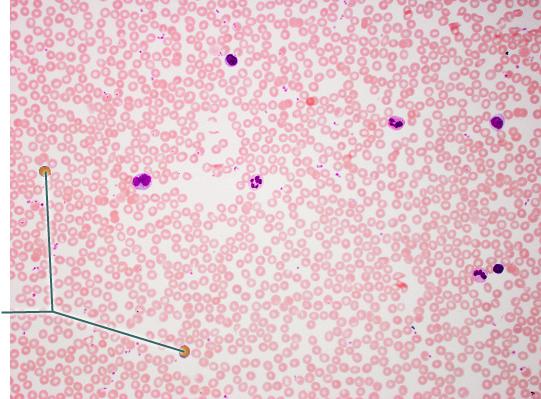

Name the tissue?

areolar

adipose

blood

bone

blood